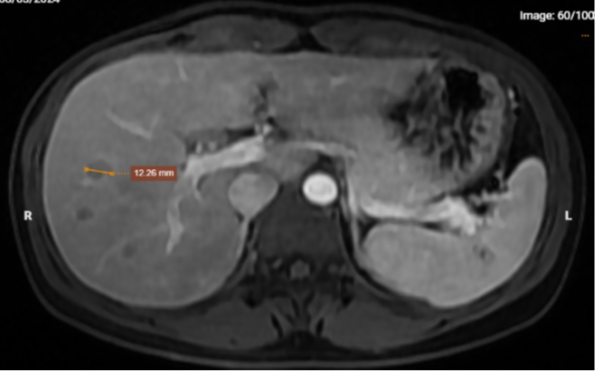

Chụp MRI phát hiện hình ảnh nhiều tổn thương dạng nốt, khối khu trú trong gan của bệnh nhân. |

Chụp MRI phát hiện nhiều tổn thương dạng nốt, khối khu trú trong gan (chủ yếu gan phải), lách, đáy phổi trái (theo dõi tổn thương do ký sinh trùng). Đồng thời, chụp CT ghi nhận hình ảnh tổn thương rải rác nhu mô phổi hai bên (theo dõi tổn thương viêm không đặc hiệu), hạch trung thất, nốt giảm tỷ trọng nhu mô gan và lách.

Từ kết quả chụp chiếu đó cho thấy bệnh nhân có tổn thương tại gan, lách, phổi và kết quả xét nghiệm dương tính với các loại giun sán do ký sinh trùng, nên chẩn đoán xác định tổn thương gan, lách, phổi theo dõi do ký sinh trùng. Sau đó, bệnh nhân được tư vấn, điều trị ngoại trú tại Bệnh viện Bệnh Nhiệt đới Trung ương để tránh biến chứng khôn lường có thể xảy ra.